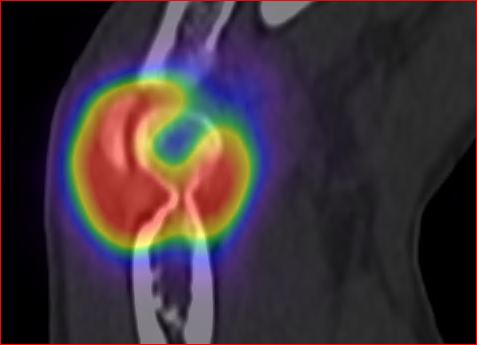

Následně provedena verifikační scintigrafie k posouzení distribuce RF - s využitím spektra brzdného záření

(obr. 5,6,7).

/ Obr.6.: SPECT/CT distribuční scintigrafie v koronárním řezu – RF v pravém loketním kloubu.